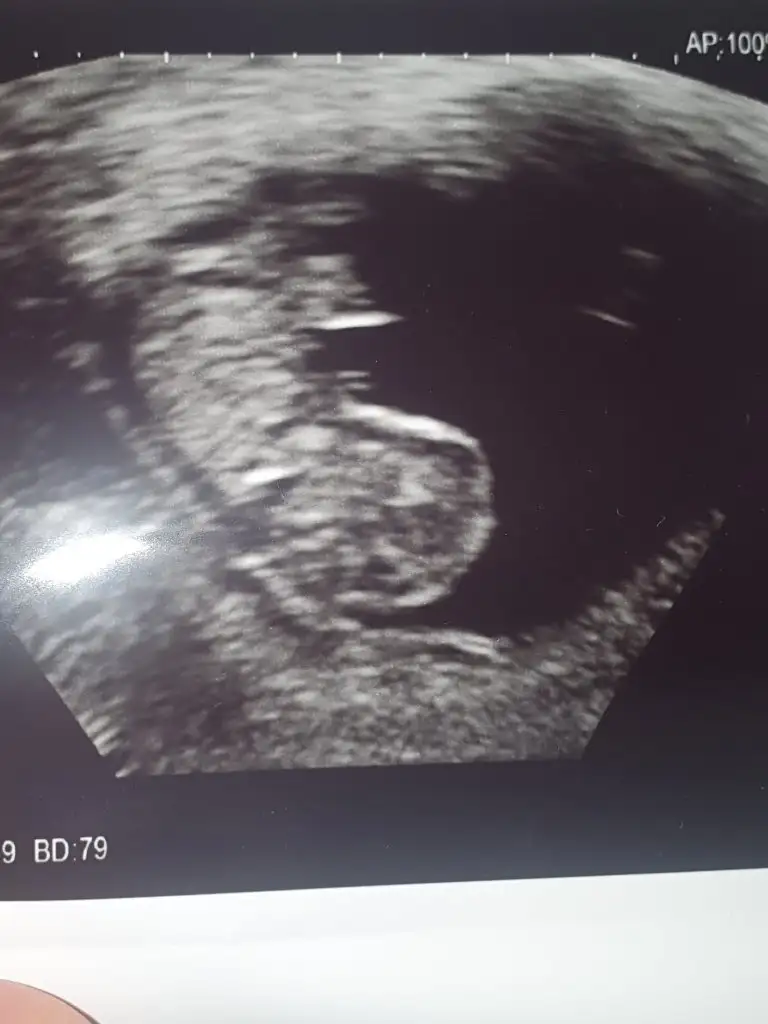

Bana da yorum yapar mısınız kızlar 5+3 günlügüz

Eklentiler

• IMG-20230406-WA0008.webp

26,2 KB · Görüntüleme: 89